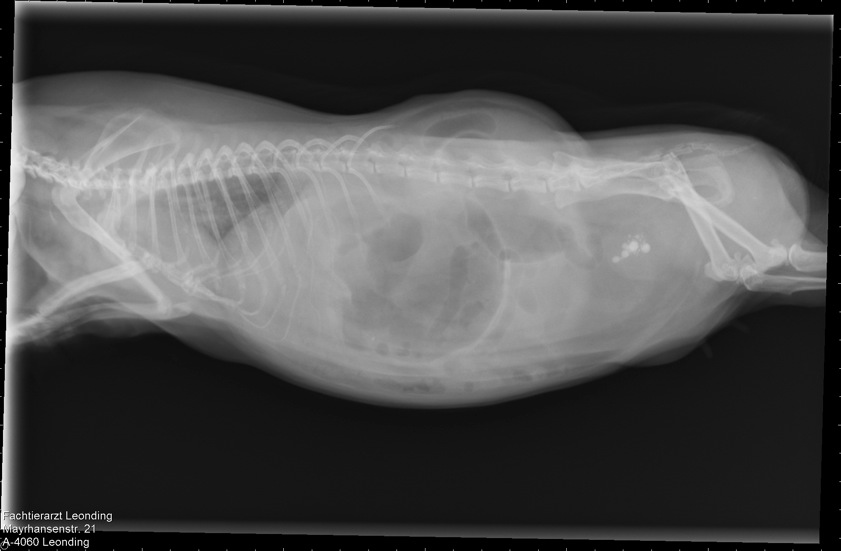

Slika 4,5 godina stare zamorčice Dixie, sa dijagnosticiranim kamencima u mjehuru, popraćenim plinovima u probavi, jer je zamorčica odbila hranu:

Terapija: Sab Simplex i ručno prihranjivanje zbog probave i razbijanja zraka. Metacam zbog bolova, 3 dana po 1 kap, zatim pauza, jer Metacam ide na bubrege. Probiotik, Pro Pre Bac, zatim kašica od kakice zdravog zamorčića.

Nakon tjedan dana, započeta terapija antibiotikom, Enrofloxacin, 0,1ml na dan

Popraćena terapijom za razbijanje kamenaca, Lysium™, 300 mg Tablete, 2 tablete na dan.

Čajevi od crnog sljeza za oporavak sluznice u crijevima i mjehuru, čaj od koprive, čaj od komorača i anisa kao baza za kašice.

Novalgin kapi 500mg/ml, 1-2 kapi na dan, po potrebi, za olakšavanje boli.

Dixie i dalje odbija sama jesti. Zadržava se u toploj vreći koja je postavljena na stalno zagrijavani Snuggle Safe jastučić. Očito ima temperaturu, pa joj toplina odgovara. Odvojena je ogradicom od ostalih zamorčića, kako bi bila pod kontrolom.